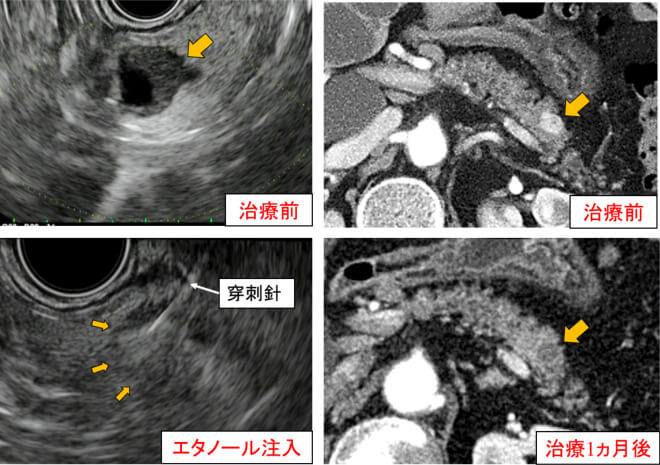

膵神経内分泌腫瘍(NET)に対する超音波内視鏡下エタノール注入療法

2cm以下の膵NET(G1)と診断した症例で、耐術能が乏しい、もしくは手術の希望がない方を対象としております。

膵神経内分泌腫瘍(NET)に対する超音波内視鏡下エタノール注入療法 治療前から治療1か月後までの経過レントゲン